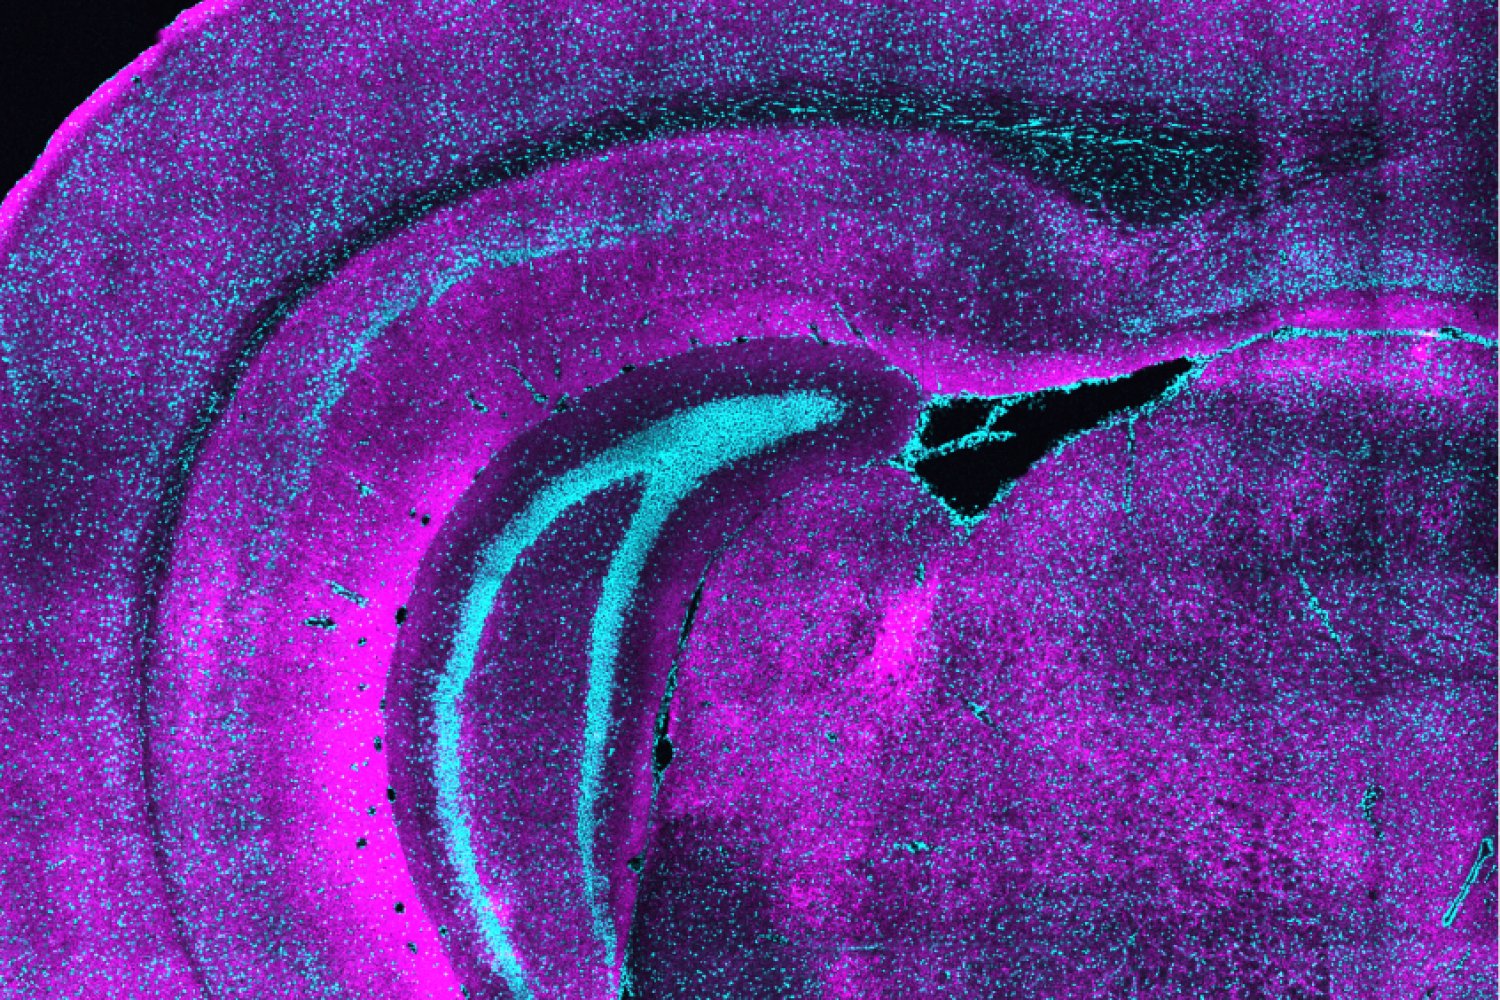

How a unique class of neurons may set the table for brain development